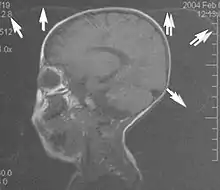

A motion artifact is one of the most common artifacts in MR imaging.[2] Motion can cause either ghost images or diffuse image noise in the phase-encoding direction. The reason for mainly affecting data sampling in the phase-encoding direction is the significant difference in the time of acquisition in the frequency- and phase-encoding directions.[1] Frequency-encoding sampling in all the rows of the matrix (128, 256 or 512) takes place during a single echo (milliseconds). Phase-encoded sampling takes several seconds, or even minutes, owing to the collection of all the k-space lines to enable Fourier analysis. Major physiological movements are of millisecond to seconds duration and thus too slow to affect frequency-encoded sampling, but they have a pronounced effect in the phase-encoding direction. Periodic movements such as cardiac movement and blood vessel or CSF pulsation cause ghost images, while non-periodic movement causes diffuse image noise (Fig. 1). Ghost image intensity increases with amplitude of movement and the signal intensity from the moving tissue. Several methods can be used to reduce motion artifacts, including patient immobilisation, cardiac and respiratory gating, signal suppression of the tissue causing the artifact, choosing the shorter dimension of the matrix as the phase-encoding direction, view-ordering or phase-reordering methods and swapping phase and frequency-encoding directions to move the artifact out of the field of interest.[1]

Flow can manifest as either an altered intravascular signal (flow enhancement or flow-related signal loss), or as flow-related artifacts (ghost images or spatial misregistration). Flow enhancement, also known as inflow effect, is caused by fully magnetised protons entering the imaged slice while the stationary protons have not fully regained their magnetization.[1] The fully magnetized protons yield a high signal in comparison with the rest of the surroundings. High velocity flow causes the protons entering the image to be removed from it by the time the 180-degree pulse is administered. The effect is that these protons do not contribute to the echo and are registered as a signal void or flow-related signal loss (Fig. 2).[1] Spatial misregistration manifests as displacement of an intravascular signal owing to position encoding of a voxel in the phase direction preceding frequency encoding by time TE/2.The intensity of the artifact is dependent on the signal intensity from the vessel, and is less apparent with increased TE.[1]